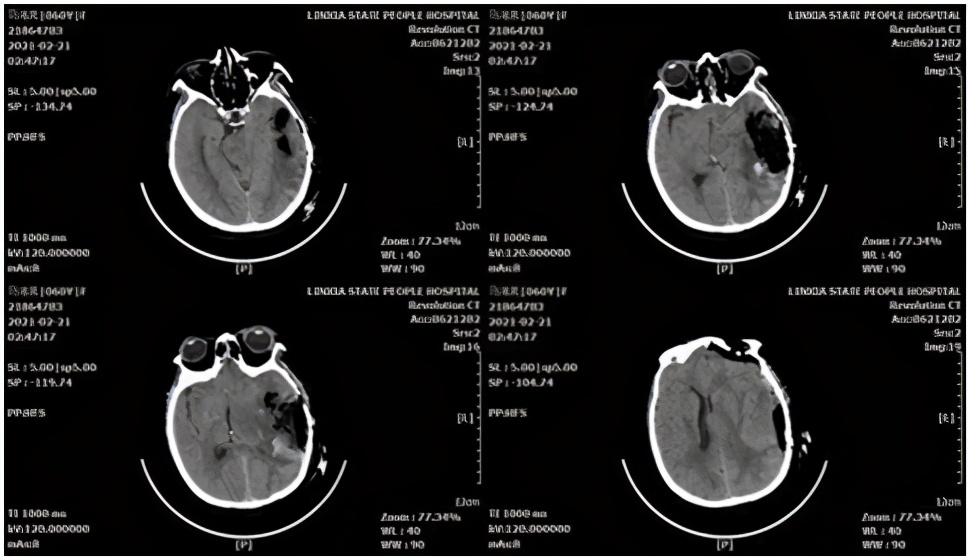

脑叶出血病例,患者女性,61岁。主因"“突发意识障碍、恶心、呕吐5小时”",于2021-02-20收入院。头颅CT示:左侧颞顶叶脑内血肿。

术前CT

术中采用微骨窗入路,保护缺血半暗带,最终 回复 良好。

术后CT